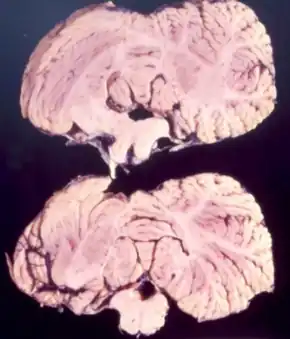

Neuropathology

Studies from Kuru infected individuals have revealed information explaining the effects that the disease can have on the brain. In the early stages of the disease, infected individuals may experience withdrawal, incoordination, tremors, and curling of the toes and feet.[14] To understand these difficulties in balance and coordination studies were conducted to analyze the brain of Kuru infected individuals. These studies by Klatzo et al., found that neurons in a Kuru infected brain were abnormally small and lighter in color compared to their healthy counterparts.[14] Affected neurons appear "moth-eaten" due to their characteristic deformations. [14] These abnormalities in the neurons of the brain of a person infected by Kuru were similar to the neurons of a brain of an individual infected with Creutzfeldt-Jakob disease (CJD).[14]